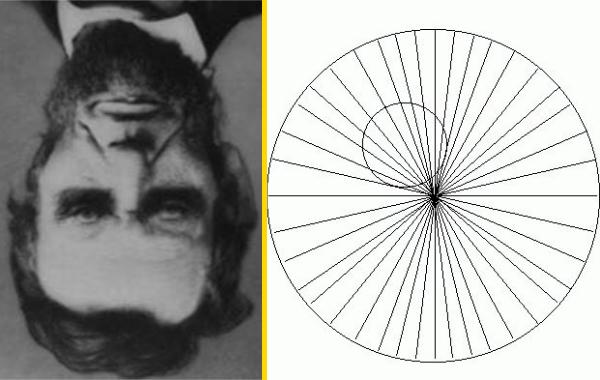

Наконечник стрелы

Рыбацкий крючок